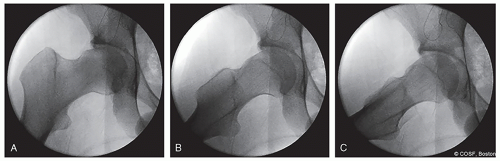

With fluoroscopy, a true anteroposterior (AP) image of the operative hip, 90° Dunn-lateral, 45° Dunn-lateral, frog-leg lateral, and false profile views of the hip are obtained preoperatively and saved (Figure 33.4)